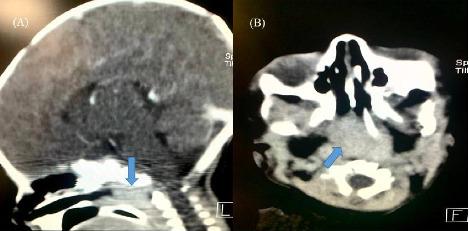

随着紫绀性呼吸暂停发作的持续时间延长,患者接受了气管插管,过程中未见肿块。据患儿母亲描述,紫绀性呼吸暂停发作通常发生在哭闹之后。心脏评估未发现异常。支气管镜检查发现后鼻孔变窄(图1)。考虑后鼻孔肿物或后鼻孔闭锁、气道软化。经过CT扫描发现鼻咽区域增强,不排除血管瘤、皮样囊肿、淋巴管瘤和畸胎瘤等肿块(见图2)。

图2 CT扫描(A)矢状图和(B)轴位图,箭头指向鼻咽部增强区

肿物测量值为24 × 25 毫米,颅底没有骨缺损,考虑血管瘤。查体见患儿口内肿物突出,排除其他部位血管瘤后行支气管镜检查显示悬雍垂全长肿块(图3)。经口入路切开软腭后发现以鼻咽区为中心的血管肿块,延伸到口咽,位于悬雍垂后(图4)。在图5中,肿块被经口取出,彻底切除肿块和悬雍垂,并烧灼止血,闭合软腭。患者继续插管5天后,第6天出现鼻腔及口腔大出血,考虑气管插管创伤引起。2天后支气管镜检查未见并发症,予以拔管。随后进行泼尼松龙治疗6个月,联合制霉菌素滴剂和普萘洛尔。患者出院并完全康复,没有出现进一步的并发症。